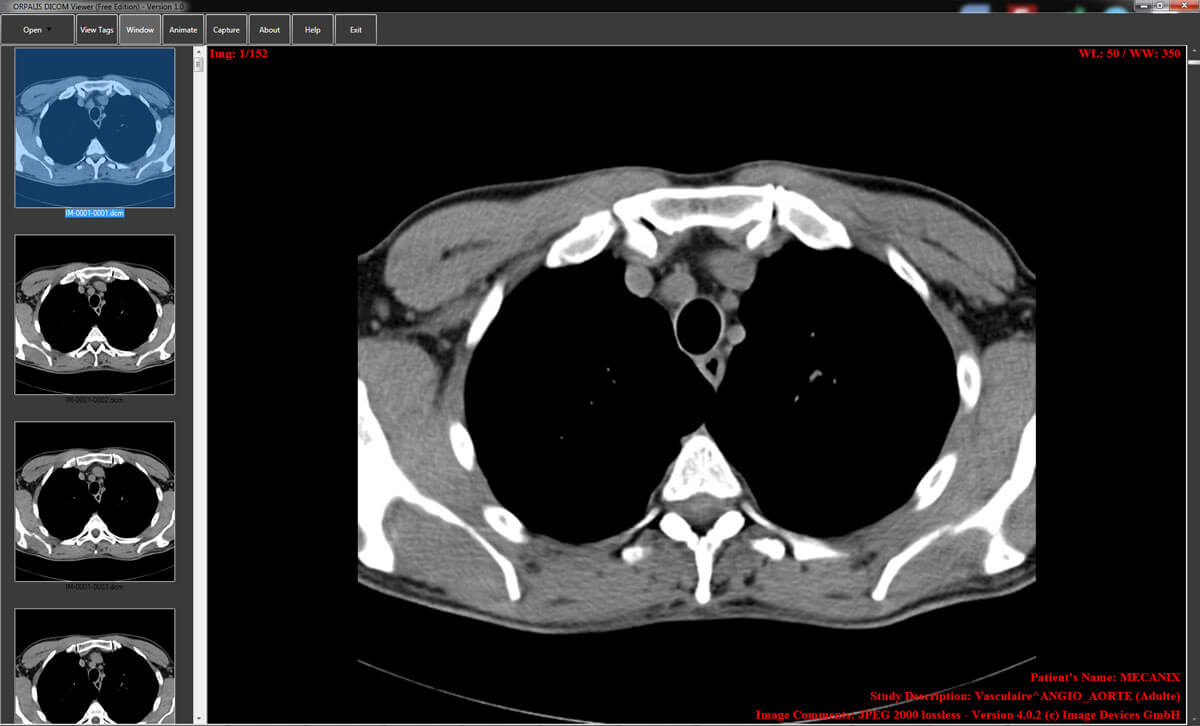

The Orpalis DICOM viewing tool supports all DICOM files and has a simple interface. There is a dedicated forum for support and problem-solving. It is capable of animating multiple frames in a loop mode for easy viewing. Images can be captured and pasted to other presentations or documents.

| 19. | Orpalis DICOM Viewer | Windows | Not available | N | N | N | Capture-paste available | 8.4 MB | Intel processor/ 2GB RAM | Freeware |